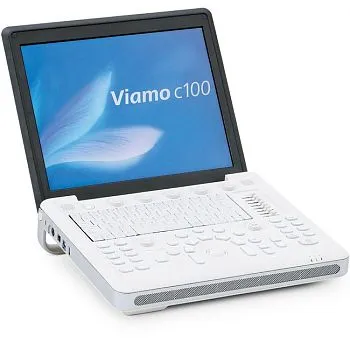

УЗИ аппарат Mindray M6 портативный

Описание